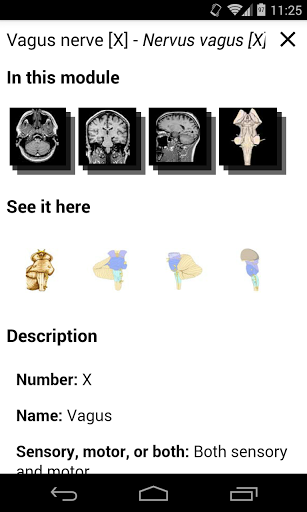

* تحسين عرض التفاصيل للأجزاء التشريحية لتسهيل التعرف عليها في صور الوحدات الحالية والوحدات الأخرى.

* تحسين رؤية تعريفات الأجزاء التشريحية

* تصفح بين الأجزاء التشريحية باستخدام روابط الوصف